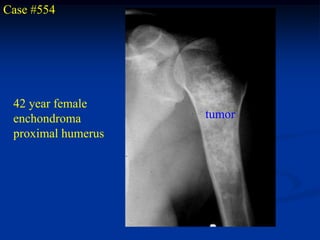

Case #554

42 year female

enchondroma        tumor

proximal humerus